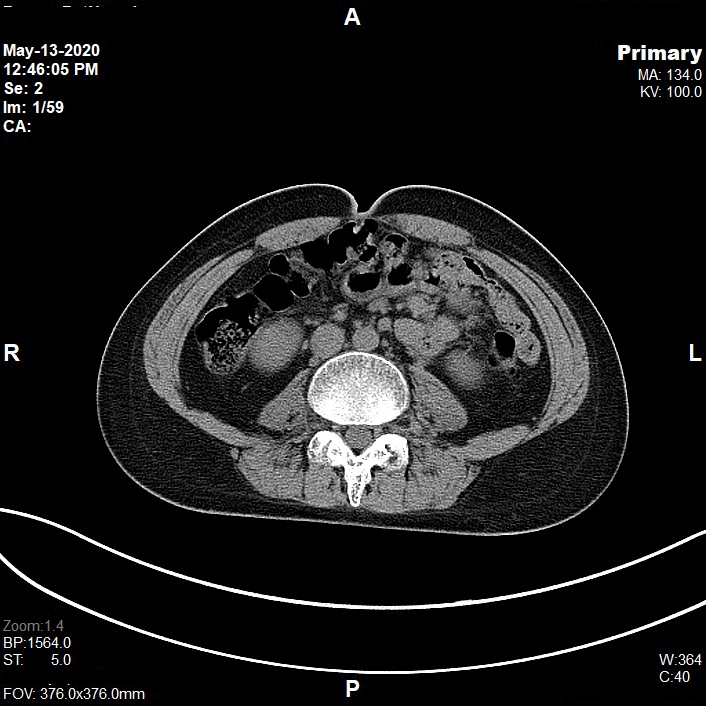

Appearance of Pelvis in Axial CT Image

CT Pelvis (Axial Images)

Non Contrast

Scanning Parameters

- kVp: 120

- mAs: Tube Current Modulation (TCM)

- Scanning Direction: Craniocaudal

- Scan Delay: 2 s

- Slice: 3.0mm (Acq. 128 x 0.6 mm)

- Image Comment: Non Contrast

- Pitch: 0.8